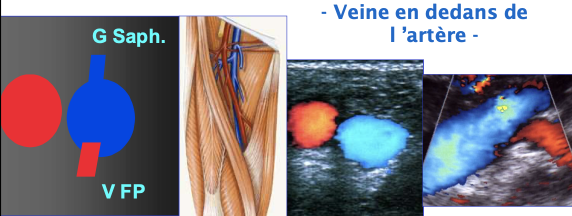

Veine fémorale commune

Crosse de la saphène (risque de TVP++ car pas de valve) → Saphène (TVS)

Veine fémorale profonde